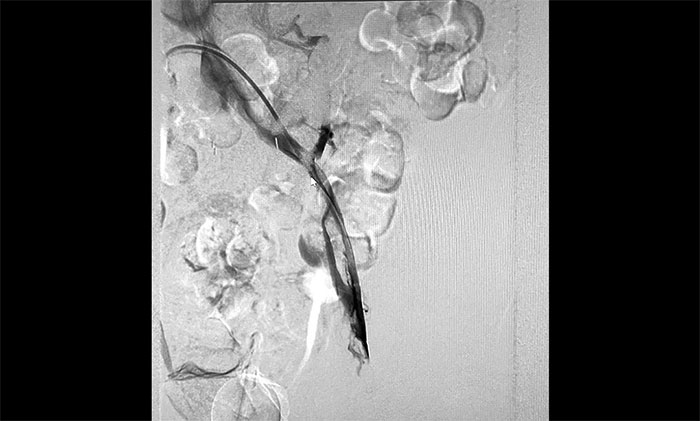

12月15日,席刚明教授在王贵平博士及介入团队协助下顺利行将一个形似伞状的人工滤器经患者右侧股静脉穿刺迅速置入肾静脉下方,“网”住了通往心血管和肺部的致命栓子,阻挡血液栓子进入肺动脉,及时挽救了患者生命。之后对病变血管进行了血栓抽吸术,及接触性溶栓,抽出了大量血栓,复查下肢造影示血栓基本消失,下肢静脉血管再通,整个手术顺利完成。术后,患者下肢肿胀好转。

▲ 下肢静脉血管顺利再通